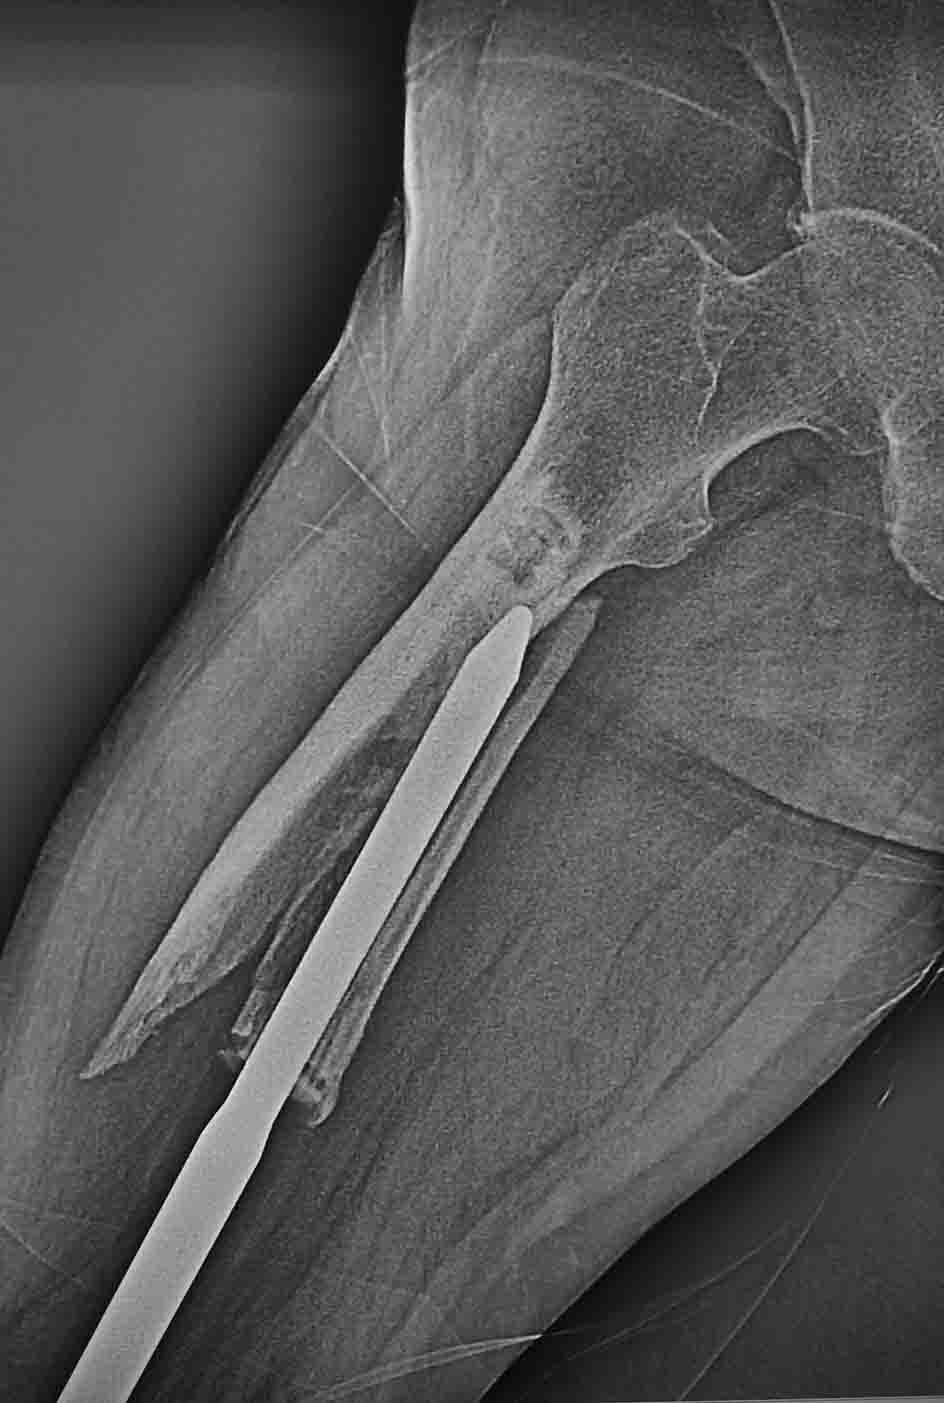

Госпитализирован пациент с перипротезным переломом бедра. Оперирован

около 5 лет назад - онкопротез коленного сустава.Какие возможны варианты

лечения, куда можно его ориентировать? Есть ли у него шансы сохранить

ногу? Спасибо.